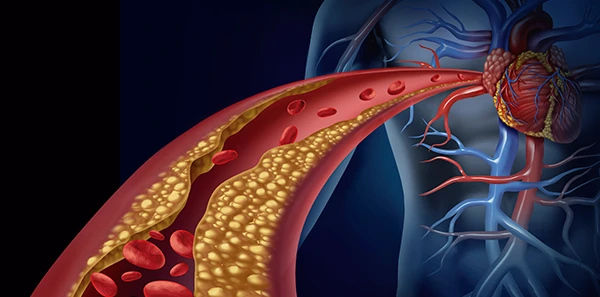

Supera los desafíos de salud cardiovascular con la ayuda de nuestros especialistas en Cardiología Intervencionista en Tabasco.

¡En Tabasco, el Dr. Carlos Aguila Bravo destaca como un cardiólogo intervencionista que utiliza métodos actualizados en cardiología! No todos los especialistas en la región se mantienen al día con las últimas técnicas practicadas en países de primer mundo, pero el Dr. Aguila Bravo es diferente. Con su compromiso en brindar la mejor atención cardiológica, te ofrece una experiencia médica vanguardista y actualizada. No te conformes con menos cuando se trata de tu salud cardiovascular. Agenda tu consulta con el Dr. Carlos Aguila Bravo en Tabasco y descubre cómo su enfoque innovador puede marcar la diferencia en tu bienestar. ¡Tu corazón merece lo mejor y él se asegurará de brindártelo!